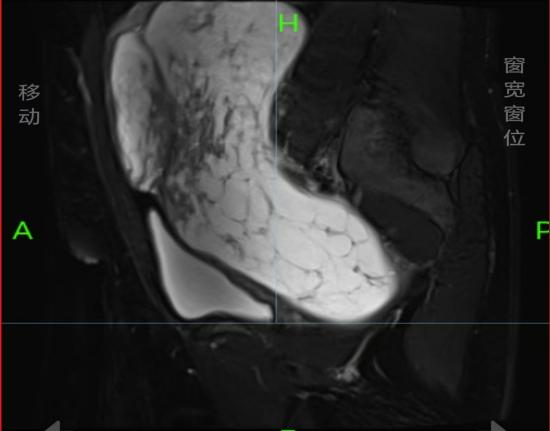

该患者因腹部胀痛伴尿频40天前来就诊,经影像学检查发现盆腔内存在一大小约22cm×20cm的巨大包块,上缘达剑突下两横指。包块来源及性质不明,血供丰富,与周围组织紧密粘连,已严重压迫膀胱、肠道等脏器,手术难度和风险极高。但为解除患者痛苦、改善生活质量,手术探查是唯一有效的治疗途径。